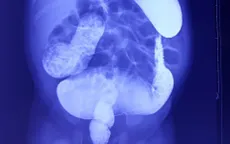

Rối loạn đại tiện, bé 18 tháng phát hiện dị tật bẩm sinh có tỷ lệ tử vong đến 80% VTV.vn - Từ khi sinh ra đến nay đã được hơn 18 tháng tuổi, bệnh nhi A.P.V.H. luôn gặp vấn đề về rối loạn đại tiện.

Quảng Trị: Lần đầu phẫu thuật Soave điều trị bệnh phình đại tràng bẩm sinh VTV.vn - Bệnh viện đa khoa tỉnh Quảng Trị vừa thực hiện ca phẫu thuật Soave cắt đoạn đại trực tràng bị phình để điều trị táo bón bẩm sinh cho bé trai 34 tháng tuổi.